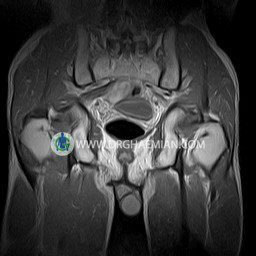

پزشکان اغلب از تصویربرداری ام آر آی برای تشخیص و درمان عارضه های پزشکی که فقط با استفاده از اشعه ایکس یا میدان مغناطیسی و امواج رادیویی قابل مشاهده است، استفاده می کنند. دستگاه ام آر آی تصاویر دقیق از ساختار های داخلی بدن ایجاد می کند. در این کیس استئومیلیت لگن، آتروز و سنیویت دیده می شود.

Technique : coronal STIR , coronal T2 , Axial T1 , axial T2 .

The femoral heads and acetabula are normal shape , signal intensity and the femoral heads are well covered by the acetabular margins .

The joint spaces are of normal width without fluid collection .

The articular surfaces are smooth and congruent and show normal cortical thickness .

– Heterogeneous signal change (high T2/STIR , low T1) in proximal metaepiphysis of left femur without articular surface irregularity suggestive for bone bruise (stress fracture?), osteomyelitis & arthritis and marrow infiltration (less probable)

– Left hip joint effusion suggestive for synovitis

are seen.